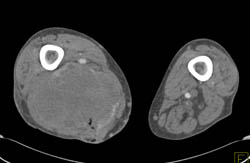

Cellulitis